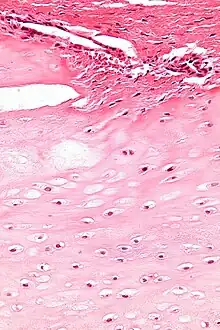

Micrograph of an enchondroma. H&E stain.